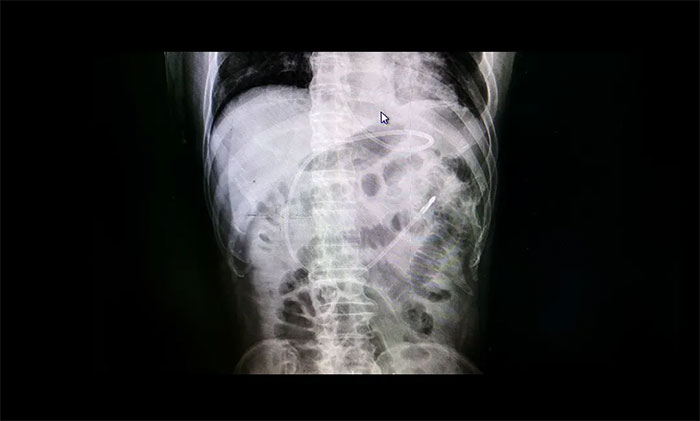

7B病区医护团队多次讨论治疗方案,结合其病情,最后决定给王先生行“床旁鼻空肠管置入术”。经管床医生与患者家属沟通交流后,患者家属同意该治疗方案。近日,李楠楠护士长带领护理团队成功为患者在床旁行鼻空肠管置入术,再经过DR验证,一个完美的“C”确证空肠管已经到达指定部位!患者开始安全“进食”。经留置鼻肠管后,患者未出现呕吐、返流等情况,肺部感染及营养状况明显好转。

▲DR验证,空肠管已经到达指定部位